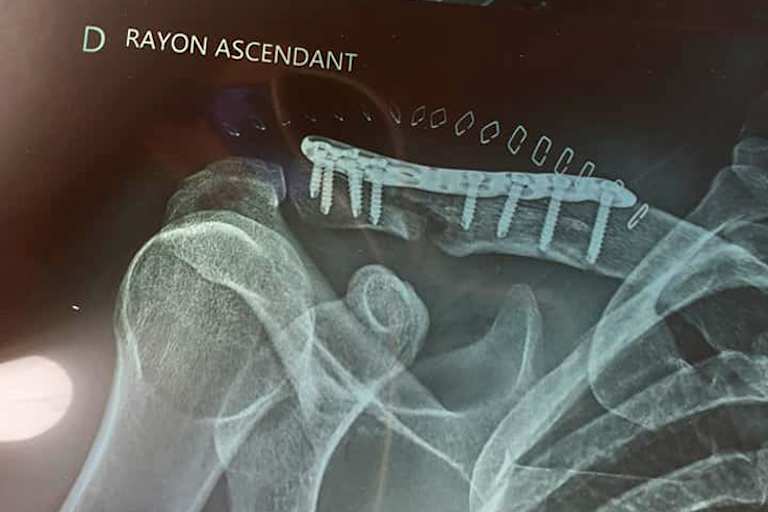

Zwischendrin hatte Gines noch eine IDM-Vertrag im Team von Werner Daemen, konnte die Saison aber nicht zu Ende fahren, da er sich bei einem unverschuldeten Sturz über eine Pilone am Schleizer Dreieck beide Arme gebrochen hatte. Sein Engagement im Team von Emil Weber im Jahr 2018 endete vorzeitig, da Gines’ Herz eher für die Langstrecke schlug. Doch auch bei Sprintrennen ist der Franzose fleißig. Am Wochenende holte er sich bei den beiden Rennen in Carole, einer Rennstrecke vor den Toren von Paris, den Titel in der Französischen Superbike-Meisterschaft. Das Ganze fand für den heute 30-Jährigen unter erschwerten Bedingungen statt. Beim Langstrecken-WM-Finale in Suzuka war noch alles bestens. Doch vor knapp zwei Wochen ging es für Gines per Hubschrauber in die Klinik. "Vor acht Tagen wurde ich dann von Dr. Dufour operiert", verrät er nach dem Titelgewinn. "Eine Platte im rechten Schlüsselbein, acht Schrauben und eine leichte Fraktur des linken Daumen galt es zu versorgen." In Carole fand nun der vorletzte Lauf der Französischen Meisterschaft statt und Gines wollte in Sachen Meisterschaft ein paar Punkte retten, bevor es im September zum Finale nach Albi geht. Doch mit einem Sieg im ersten und Platz 2 im zweiten Rennen, hinter seinem Tecmas-BMW-Teamkollegen Kenny Foray, machte Gines schon vorzeitig alles perfekt.